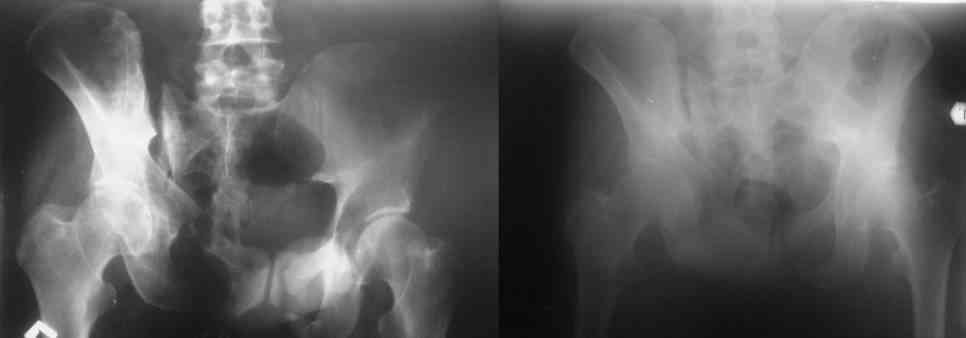

Остается только вариант закрытого аппаратного лечения. В аттаче положение отломков на вытяжении в прямой (АР) проекции. Для сравнения снимок до и во время вытяжения.

> Остается только вариант закрытого аппаратного лечения.. В аттаче

> положение отломков на вытяжении в прямой (АР) проекции. Для сравнения

> снимок до и во время вытяжения.